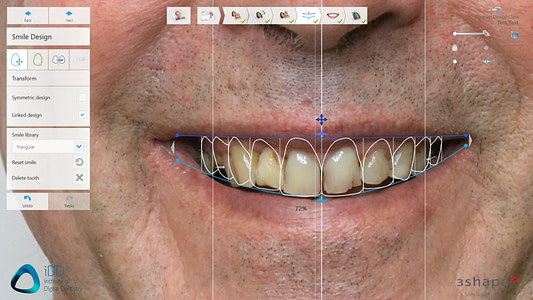

3shape Smile Design

Immerse yourself in the artistic beauty of 3shape Smile Design through substantial collections of inspiring images. blending traditional techniques with contemporary artistic interpretation. transforming ordinary subjects into extraordinary visual experiences. The 3shape Smile Design collection maintains consistent quality standards across all images. Ideal for artistic projects, creative designs, digital art, and innovative visual expressions All 3shape Smile Design images are available in high resolution with professional-grade quality, optimized for both digital and print applications, and include comprehensive metadata for easy organization and usage. Our 3shape Smile Design collection inspires creativity through unique compositions and artistic perspectives. Instant download capabilities enable immediate access to chosen 3shape Smile Design images. Our 3shape Smile Design database continuously expands with fresh, relevant content from skilled photographers. The 3shape Smile Design collection represents years of careful curation and professional standards. Diverse style options within the 3shape Smile Design collection suit various aesthetic preferences. Multiple resolution options ensure optimal performance across different platforms and applications. Professional licensing options accommodate both commercial and educational usage requirements. Each image in our 3shape Smile Design gallery undergoes rigorous quality assessment before inclusion. Time-saving browsing features help users locate ideal 3shape Smile Design images quickly. Advanced search capabilities make finding the perfect 3shape Smile Design image effortless and efficient.